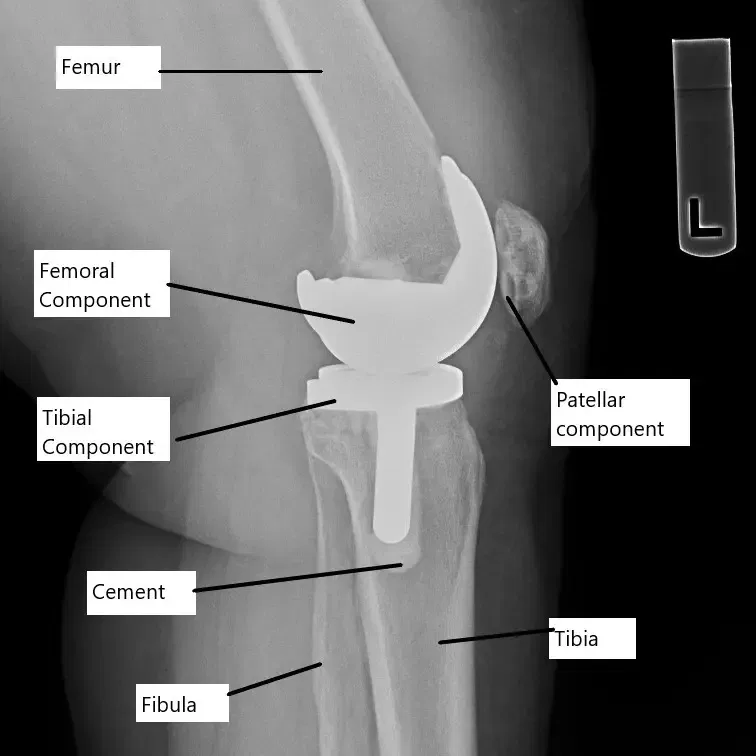

La radiografía muestra un reemplazo total de rodilla.

En la cirugía de reemplazo de rodilla, se retiran los extremos dañados del fémur (hueso del muslo) y la tibia (espinilla) y se sustituyen por componentes protésicos. Se coloca un inserto de plástico entre las piezas metálicas para reducir la fricción. Esta articulación artificial está diseñada para imitar la función natural de la rodilla, permitiendo un movimiento suave y un apoyo de peso. Cuando el dolor persiste, puede deberse a problemas con el implante o las estructuras circundantes.